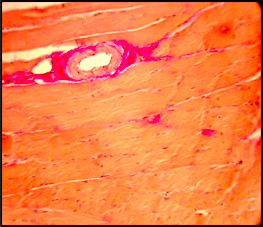

Оказалось по Газу и Макнабу что питающая надкостницу вена гораздо тоньше питающей артерии.

Поэтому кровь уходит куда-то в другое место.

На самом деле она сохраняется в гаверсовых системах и выходит через сосуды надкостницы.

Две трети внутреннего слоя компактной кости питаются артерией и одна треть - сосудами надкостницы.